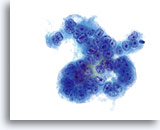

Er kan veelvuldig insnoeren worden waargenomen in zowel endocervicaal adenocarcinoom, als in endometriaal adenocarcinoom.

60x